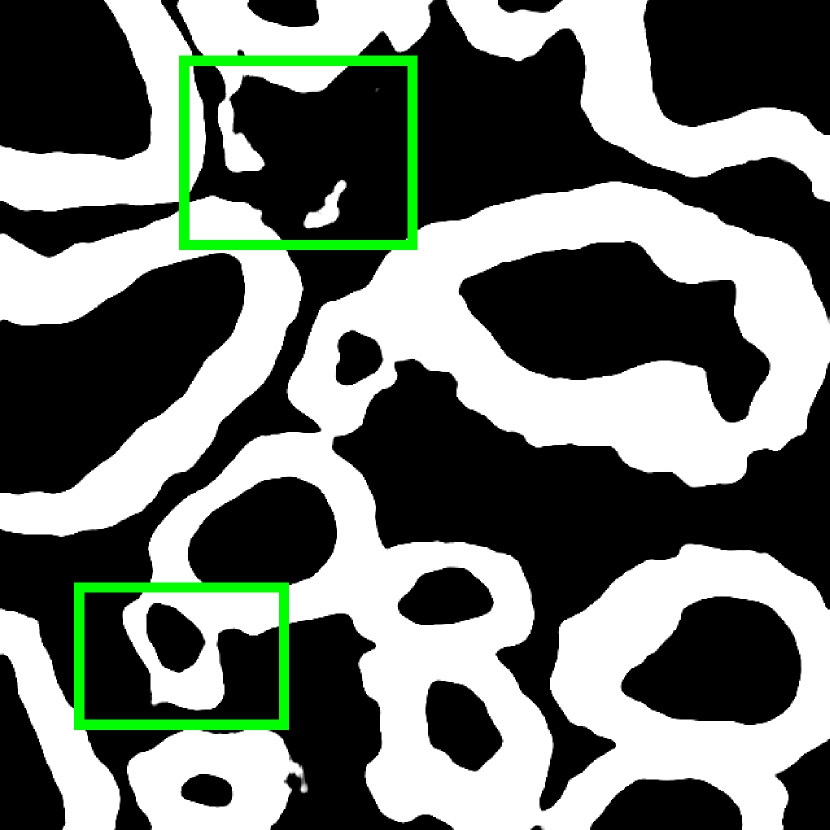

Fig. 3 shows two image examples, their ground-truth masks, and the final segmentations generated by competing models. Comparing with U-Net, Res-Seg based models generally have fewer false positives. Comparing with Res-Seg-Net, Res-Seg-Net and Res-Seg-Net both generate cleaner outputs, which can serve as an evidence that hierarchical refinings are effective in improving segmentations in both accuracy and robustness. These effects can be clearly seen within the areas highlighted with green boxes.